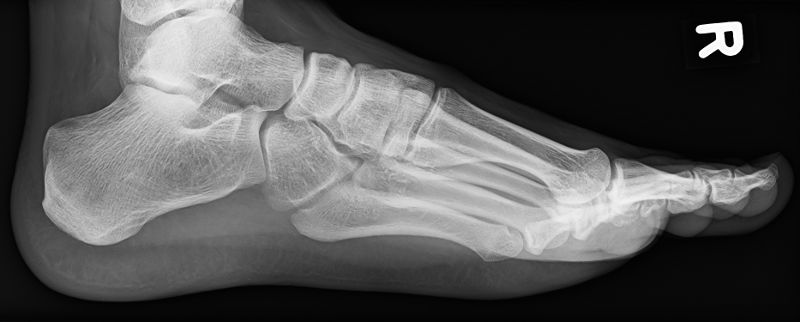

Behandlungsbeispiel

Die Orthovolttherapie ist eine schmerzfreie, nichtinvasive Behandlung mit speziellen energetischen Röntgenstrahlen.

Sie vereinabren telefonisch oder persönlich einen Termin mit uns und bringen zur Erstvorstelldung bitte Ihre Versichertenkarte und Überweisung und, falls vorhanden, auch Röntgenbilder der zu bestrahlenden Körperregion mit.